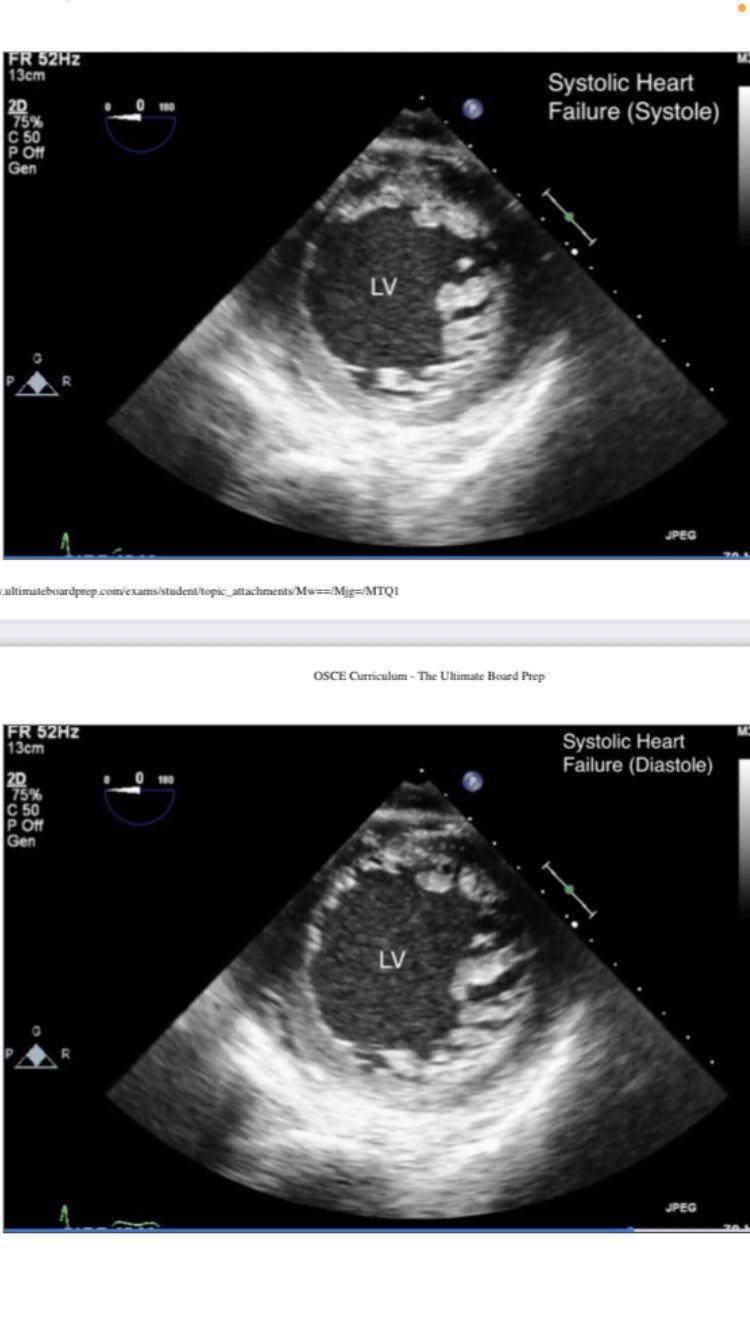

transgastric mid SAX view

systole and disatole

hypovolemia, very little movement/filling

transgastric midpapillary SAX